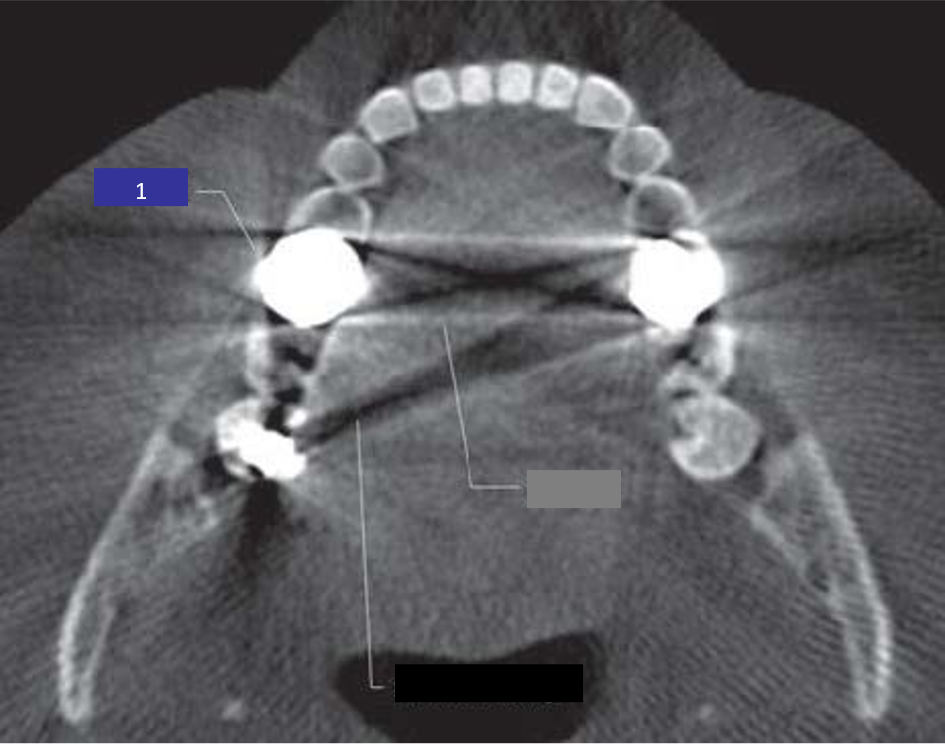

35) Identify the cone beam artifact indicated by 1 in this image? (1 mark)

36) Identify the cone beam artifact indicated by 2 in this image? (1 mark)

37) Identify the cone beam artifact indicated by 3 in this image? (1 mark)